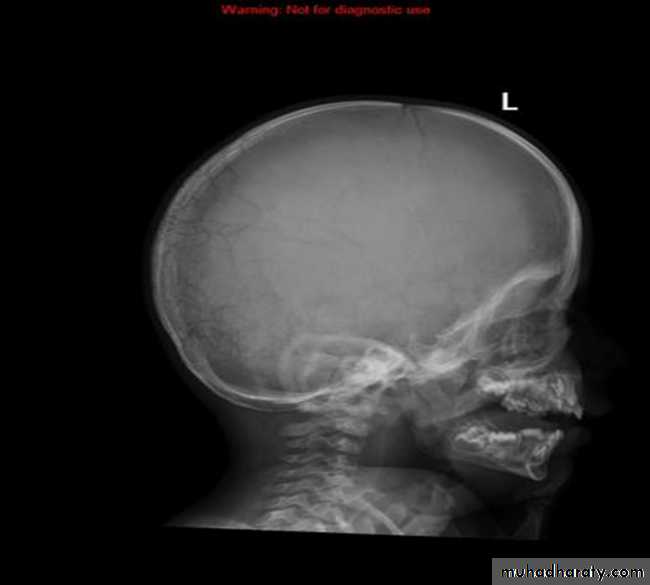

Wormian bone are a subset of the small intra sutural bones that lie between the cranial sutures mainly seen around the lambdiod sutures

Wormian bone : What is it being ??? Wormian bone are a subset of the small intra sutural bones that lie between the cranial sutures mainly seen around the lambdiod sutures

Causes ?????

osteogenesis imperfecta

rickets

cleidocranial dysostosis

Hypothyroidism

Down syndrum